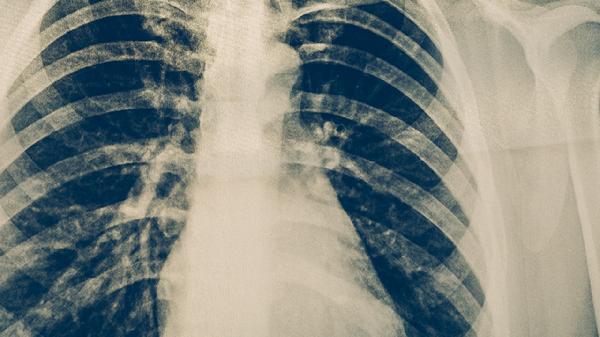

2. 肝功能损害

利福平胶囊与异烟肼片联用可能损伤肝细胞,导致胆红素代谢异常引发皮肤瘙痒,伴随乏力、食欲减退。需监测谷丙转氨酶等指标,必要时加用复方甘草酸苷片护肝。若ALT超过正常值3倍应暂停抗结核治疗。